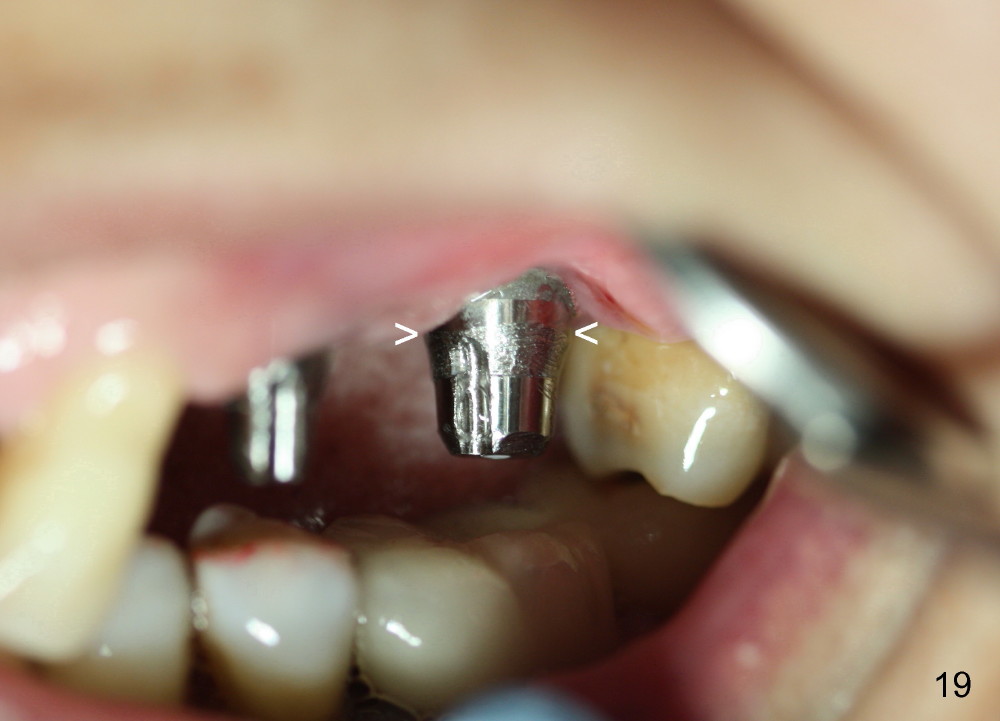

Two PAs are taken 5 months postop (Fig.15,16). Patterns of bone graft (*) between these PAs are different, which suggests presence of the graft buccal to the implant at the site of #14. Another piece of evidence of the graft is that the buccal socket heals (Fig.17 B) without implant thread exposure (Fig.19). These two implants are ready for definitive restoration (Fig.18-20). Fig.21 shows the final restoration 5 months post cementation.